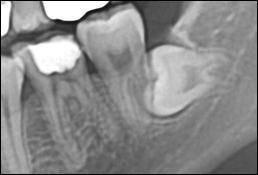

매복된 사랑니는 뽑을 때 나올 공간이 모자라기 때문에 다른 치아와는 다르게 수술적인 방법이 필요하다.

먼저 잇몸을 열고 위의 그럼처럼 치아를 머리 부분과 뿌리 부분으로 조각내고 각각 따로 따로 꺼낸 다음 열었던 잇몸을 봉합해 주는 순서다. 경우에 따라서는 사랑니 주변의 뼈를 갈아내거나 치아를 여러 조각으로 갈아야 할 수도 있다.

사진에서 붉은 화살표로 표시한 것은 '하악관'이라 불려지는 구조물로 그 안에 신경(하치조 신경)과 동맥이 들어 있다. 사진에서처럼 사랑니의 뿌리 끝과 매우 가까운 경우가 많고 따라서 신경 손상의 위험은 늘 존재한다.